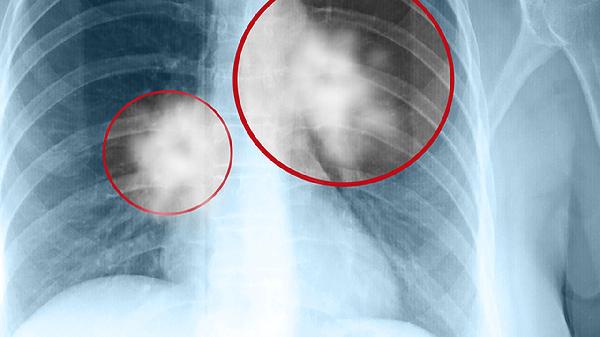

肺結(jié)節(jié)和結(jié)節(jié)影不完全相同,肺結(jié)節(jié)是影像學(xué)上直徑不超過(guò)30毫米的局灶性圓形致密影,結(jié)節(jié)影則泛指影像報(bào)告中所有結(jié)節(jié)狀陰影的描述術(shù)語(yǔ)。肺結(jié)節(jié)可能是良性病變或早期肺癌,結(jié)節(jié)影涵蓋范圍更廣,包括炎性假瘤、結(jié)核球、轉(zhuǎn)移瘤等多種病因。

肺結(jié)節(jié)特指肺部出現(xiàn)的孤立性圓形病灶,邊界清晰,直徑通常為3-30毫米。這類病變?cè)贑T檢查中表現(xiàn)為密度增高影,根據(jù)密度可分為實(shí)性結(jié)節(jié)、部分實(shí)性結(jié)節(jié)和磨玻璃結(jié)節(jié)。臨床評(píng)估需結(jié)合結(jié)節(jié)大小、形態(tài)、生長(zhǎng)速度等特征,8毫米以上的結(jié)節(jié)或伴有分葉、毛刺等惡性征象時(shí)需密切隨訪。常見(jiàn)病因包括陳舊性結(jié)核、肉芽腫性炎、錯(cuò)構(gòu)瘤等良性病變,以及肺腺癌等惡性病變。

結(jié)節(jié)影作為影像描述術(shù)語(yǔ),可出現(xiàn)在X光、CT等多種檢查報(bào)告中,既可能對(duì)應(yīng)真正的結(jié)節(jié)病灶,也可能是血管斷面、胸膜斑塊等偽影。其成因除肺結(jié)節(jié)包含的病因外,還涉及塵肺結(jié)節(jié)、類風(fēng)濕結(jié)節(jié)、寄生蟲感染等特殊類型。影像科醫(yī)生通常會(huì)在報(bào)告中注明結(jié)節(jié)影的具體特征,如鈣化灶、衛(wèi)星灶等輔助判斷性質(zhì)的細(xì)節(jié),臨床需結(jié)合實(shí)驗(yàn)室檢查與病理結(jié)果明確診斷。